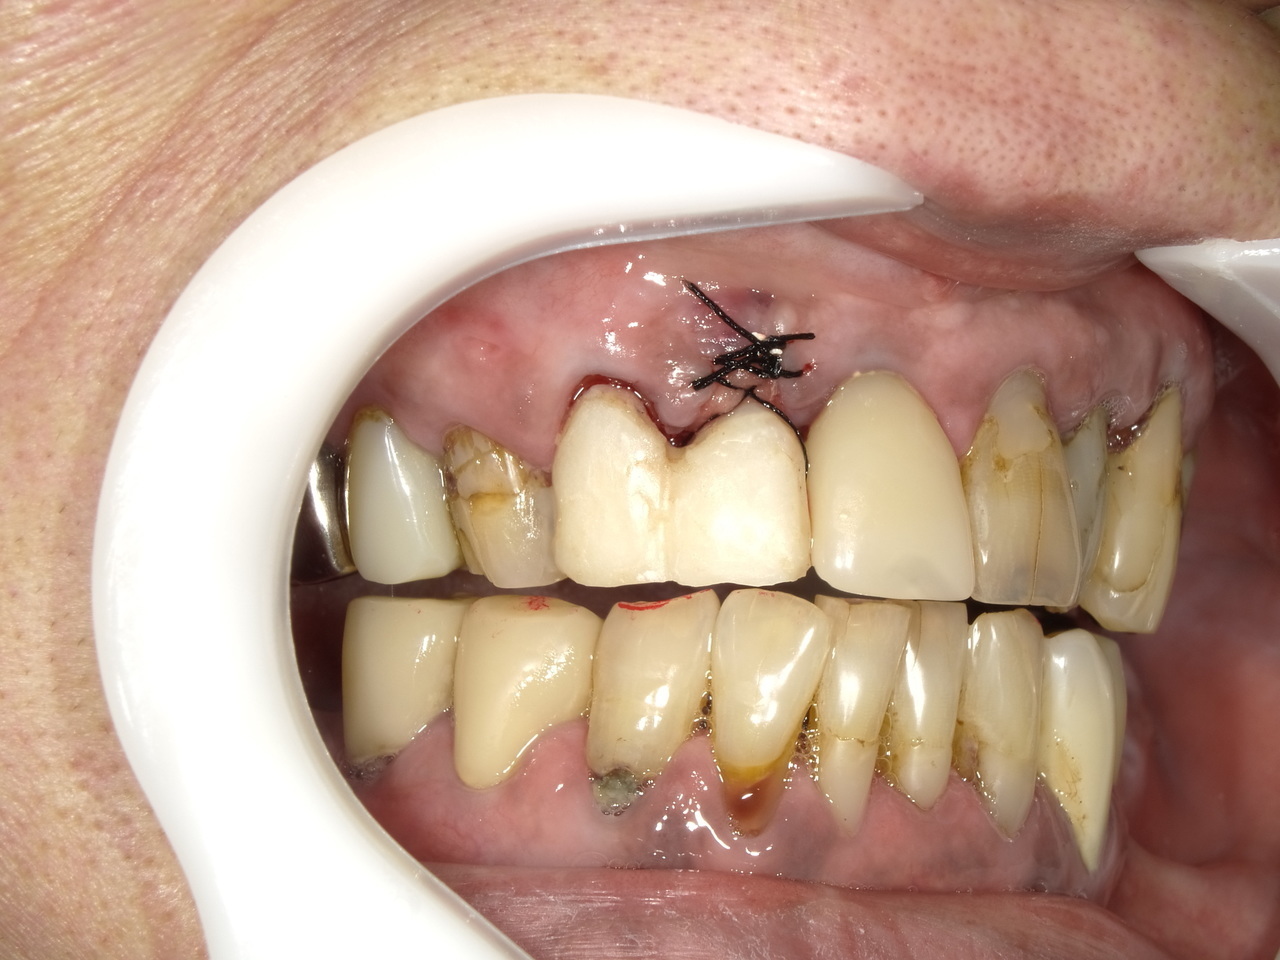

1.外傷で、歯根破折した前歯の治療を2.5か月で治療を完結したケース

症状としては、外傷のために、右上1番が歯根破折を起こしていた。

治療法としては、レントゲン等の診断の結果、歯が根元まで折れているため、抜歯が必要となったため、インプラント治療をご希望された。治療内容としては、その日に抜歯を行い、当日にインプラントの仮歯までを装着しています。その後、口腔内スキャナーで印象を行い、最終ジルコニアクラウンで最終補綴を行っています。

治療結果として、2.5か月で抜歯から最終補綴までの治療が完了できました。かみ合わせの関係で、仮歯がは破折して、ご迷惑をおかけしたこともありましたが、通常の2.5か月で治療をおえることができ、歯肉の形態と歯の形態を隣の前歯と調和する形態に整えることができました。

治療の期間・回数:治療期間2.5か月 6回の治療回数

治療の価格:385000円(税込)

治療費の内訳:インプラント基本料(フィックスチャー及び手術費用、投薬費用、レントゲン費用、インプラント上部費用(アバットメントおよびジルコニアクラウンの費用用)330000円。 抜歯即時埋入・即時負荷加算(プロビショナルレストレーション費用・人工骨費用・暫間アバットメント費用・抜歯費用を含む)55000円(税込)

治療のリスクや副作用:手術後に、痛みや腫れ、出血、合併症などを引き起こす可能性があります。噛む感覚がご自身の歯と異なる場合があります。見た目がご自身の歯と異なる場合があります。手術後にメインテナンスを継続しないと、インプラントが抜け落ちる可能性があります。